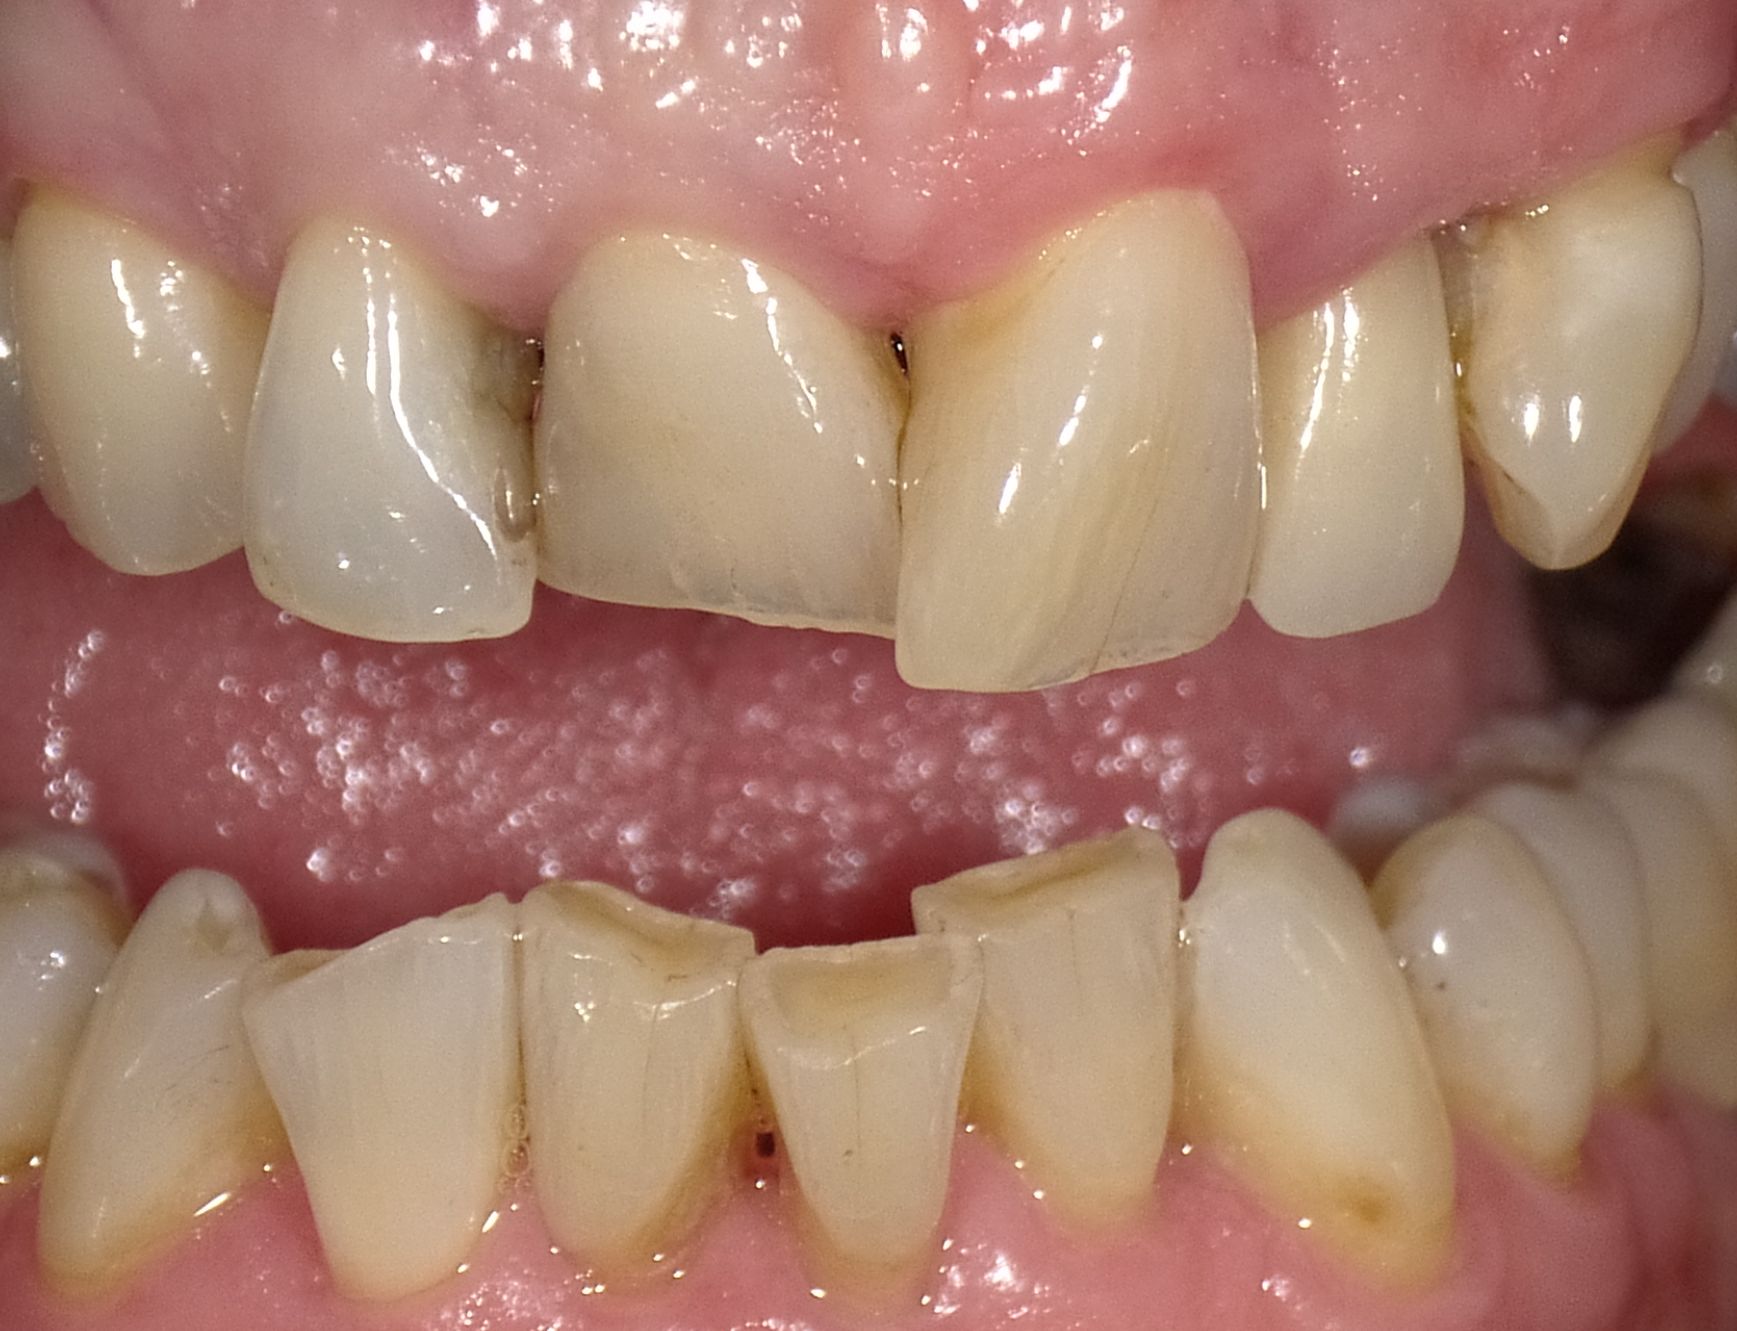

Zahnfehlstellungen und teilweise nicht mehr erhaltungsfähige Zähne durch immer wieder durchgeführte Reparaturen ohne Konzept nach Kassenrichtlinien

Vorher: Zahnfehlstellungen und teilweise nicht mehr erhaltungsfähige Zähne durch immer wieder durchgeführte Reparaturen ohne Konzept nach Kassenrichtlinien

Idealisierung im Rahmen einer Komplettbehandlung mit Vollkeramik; Ersatz der nicht erhaltungsfähigen Zähne durch Implantate

Nachher: Idealisierung im Rahmen einer Komplettbehandlung mit Vollkeramik; Ersatz der nicht erhaltungsfähigen Zähne durch Implantate